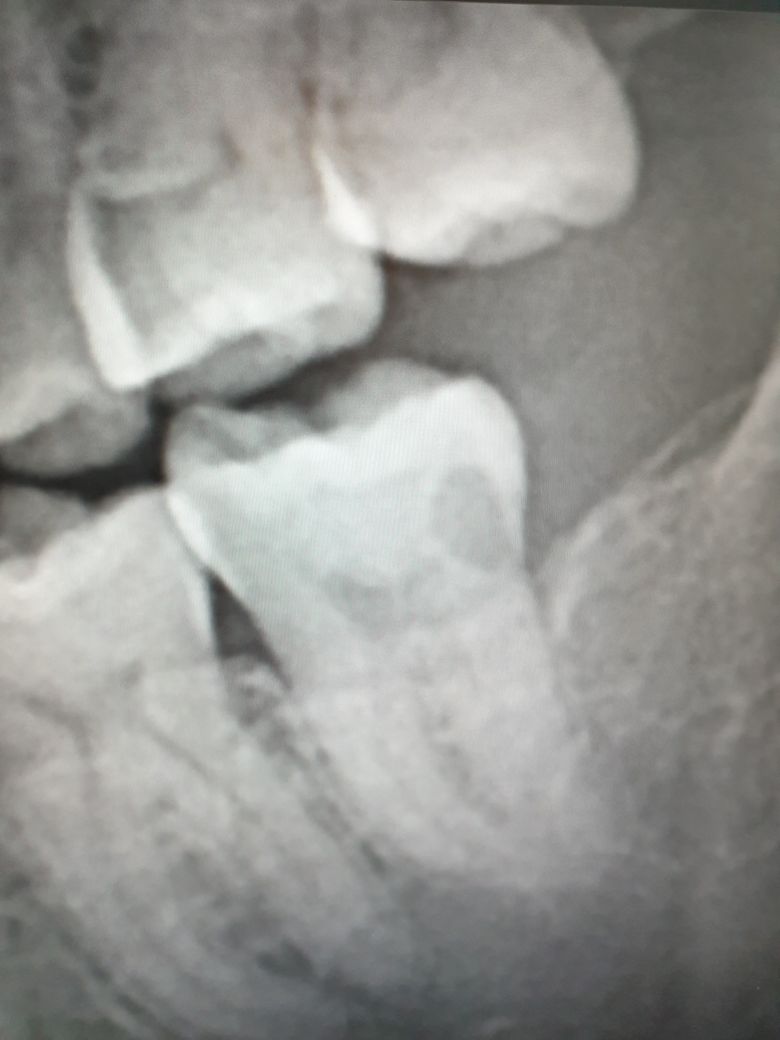

사진은 저의 이빨 상태이고, 위치는 왼쪽 맨 뒤 어금니입니다.

치과에서 X-RAY 찍어보니 저렇게 나오고 검정색 부분이 충치라고 하셨습니다.

의사 선생님께선 '신경치료'가 필요하다고 말씀하시는데요.

충치가 굉장히 깊고 안좋은 부분이 썩어 잇네요. 저정도 충치라면 신경치료를 받으셔야될것같습니다.

신경치료가 필요해보이며 발치를 하는 것보다는 최대한 본인의 치아를 보존해보시는 것이 좋겠습니다.